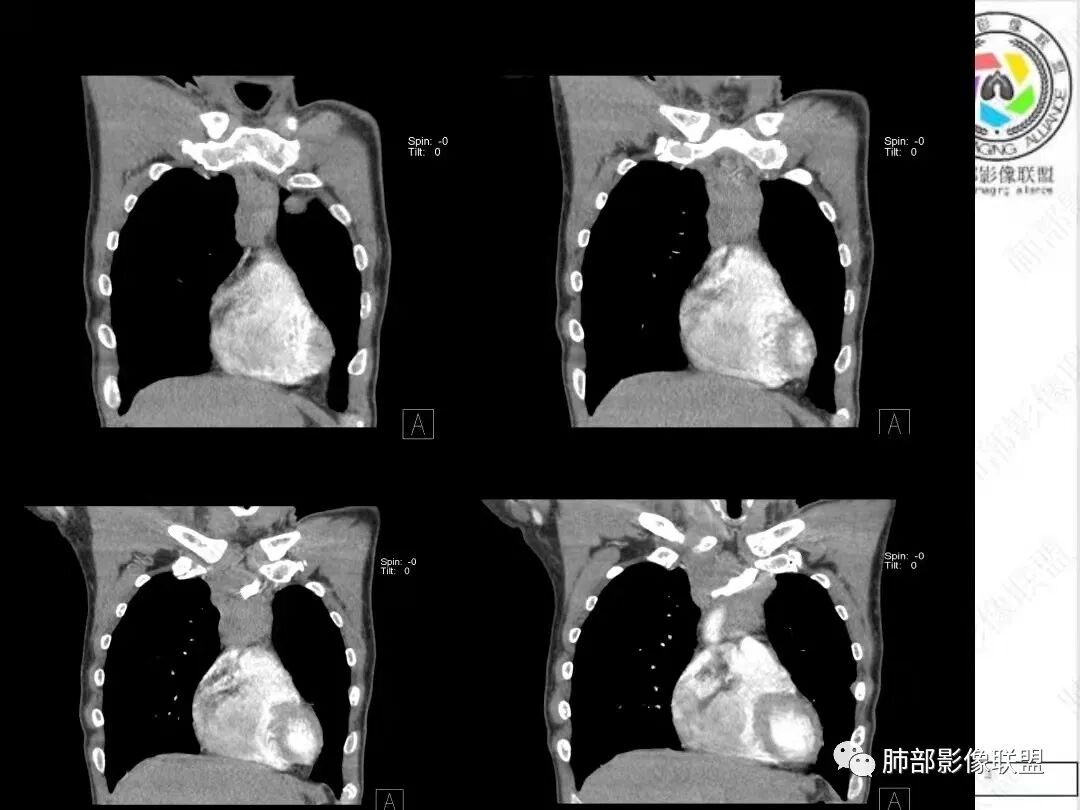

2、影像特点:胸部CT:平扫,前纵隔肿物,基本居中,与周围结构局部分界不清。增强后显示轻中度强化。肿块沿血管间隙侵袭性生长,左无名静脉受压明显变形受侵。纵隔、右肺门多处大小不等淋巴结,左侧内乳淋巴结稍增大。右侧瘤肺交界面光滑,左侧凹陷,肺组织未见明显受侵。右肺中下叶可疑小结节。胸椎及肋骨骨质增生性破坏。肋骨骨折。

病理结果:胸腺不典型类癌。

3、病例小结:  病人以胸痛就诊,无明显内分泌症状;前纵隔该部位肿瘤,胸腺瘤常见,乳酸脱氢酶偏高,55岁的年龄也较符合胸腺瘤,但胸腺瘤较少侵犯甚至包绕大血管生长、少有淋巴结肿大。

很多老师提到前纵隔占位+血管肿块内漂浮+内乳淋巴结增大+轻中度强化=淋巴瘤,淋巴瘤确有上述特点,但本例血管漂浮不明确,病灶强化不均匀,胸椎及肋骨可疑增生性转移,应想到胸腺癌或不典型类癌的可能性。

胸腺类癌好发于40~60岁男性,男女比例约为3:1。胸腺类癌侵袭性较胸腺癌低,属于低至中等程度恶性肿瘤。但是约80%侵犯邻近组织结构,20%~40%发生胸内淋巴结或远处转移,转移部位主要包括肺脏、骨、肝脏、脑等,一般表现为椎体成骨性转移。胸腺类癌影像特征:呈现纵隔偏侧性的生长,形态不规则,肿块体积通常较大,内见片状坏死区,增强扫描轻中度不均匀渐进性强化。肿瘤内部可见细丝状明显强化小血管影,推测此征象可能在胸腺类癌的诊断中有提示作用。肿瘤边界常不清晰,沿血管间隙侵袭性生长,易侵犯邻近纵隔大血管、心包、气管、食管等结构。钙化少见。